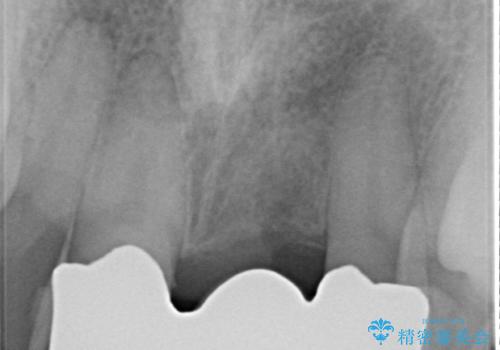

- 以前、前歯にボールが当たりダメになってしまって抜歯したが、そこにとりあえず接着剤で歯をつけて生活していたとのこと。

両側の歯の接着剤の周りが虫歯になってしまっていました。

両側の歯の虫歯をしっかりとってブリッジにすることにしました。

欠損部に長年薄いプラスチックの仮の歯を留めていたため、下の歯が食い込みさらにブリッジのポンティックの隙間がない状態でした。そのため、かみ合わせが深く、下の歯との隙間がかなりなかった為、事前の矯正治療をお勧めしましたが、希望されず特に行わずそのまま虫歯治療を行うことになりました。

かみ合わせが深く、歯ぎしりでブリッジに負担がかかるため、ナイトガードを作成し、就寝時使用していただいています。